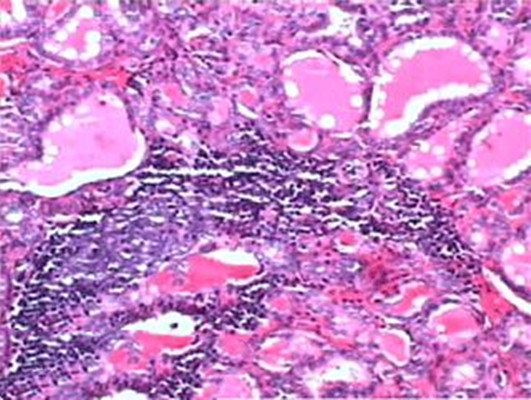

弥散淋巴组织(diffuselymphoidtissue)无固定的形态,是以网状细胞和网状纤维形成支架,网孔中分布有大量松散的淋巴细胞,与周围的结缔组织无明显分界,其中除含有T、B淋巴细胞外,还有浆细胞和巨噬细胞、肥大细胞等。弥散淋巴组织中有毛细血管后微静脉(postcapillaryvenule),其特征是内皮为单层立方或矮柱状,故又称高内皮微静脉(highendothelialvenule),是淋巴细胞由血液进人淋巴组织的重要通道。当弥散淋巴组织受抗原刺激时,可出现淋巴小结。